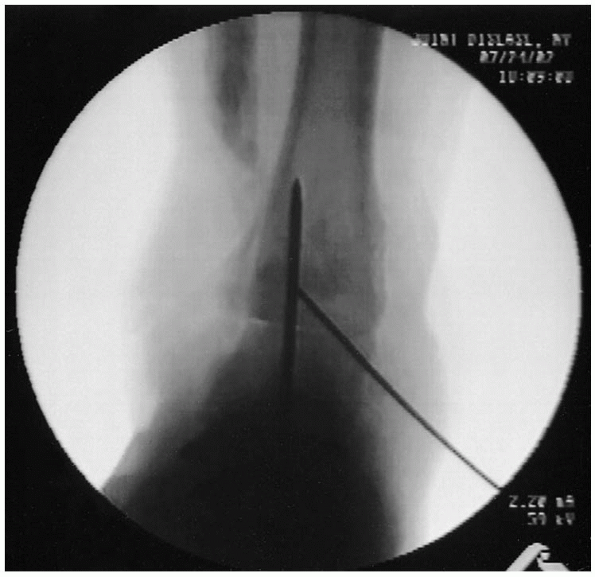

A second, smaller Kirschner wire is placed across the tibiotalar articulation for rotational control (Fig. 32-11).At this point, the position of the fusion is checked radiographically

on anteroposterior, lateral, and mortise views. With acceptable

alignment achieved, the guide wires for the cannulated screws are

placed. These can be 6.5-, 7.3-, or 8.0-mm, cannulated, partially

threaded cancellous screws, depending on the size of the patient. Two

screws are placed from proximal to distal aspects. The proximal, medial

guide wire is placed approximately 2 cm above the articular surface,

about 5 mm posterior to the midaxis of the tibia and angling about 60

degrees toward the anterolateral talus.

The second wire is placed 2 cm proximal to the joint on the lateral

side and 5 mm anterior to the midaxis of the tibia and is angled

posteromedially into the talus.

The third wire starts distally and enters the talus anterolaterally, and it is angled proximally into the posteromedial tibia.